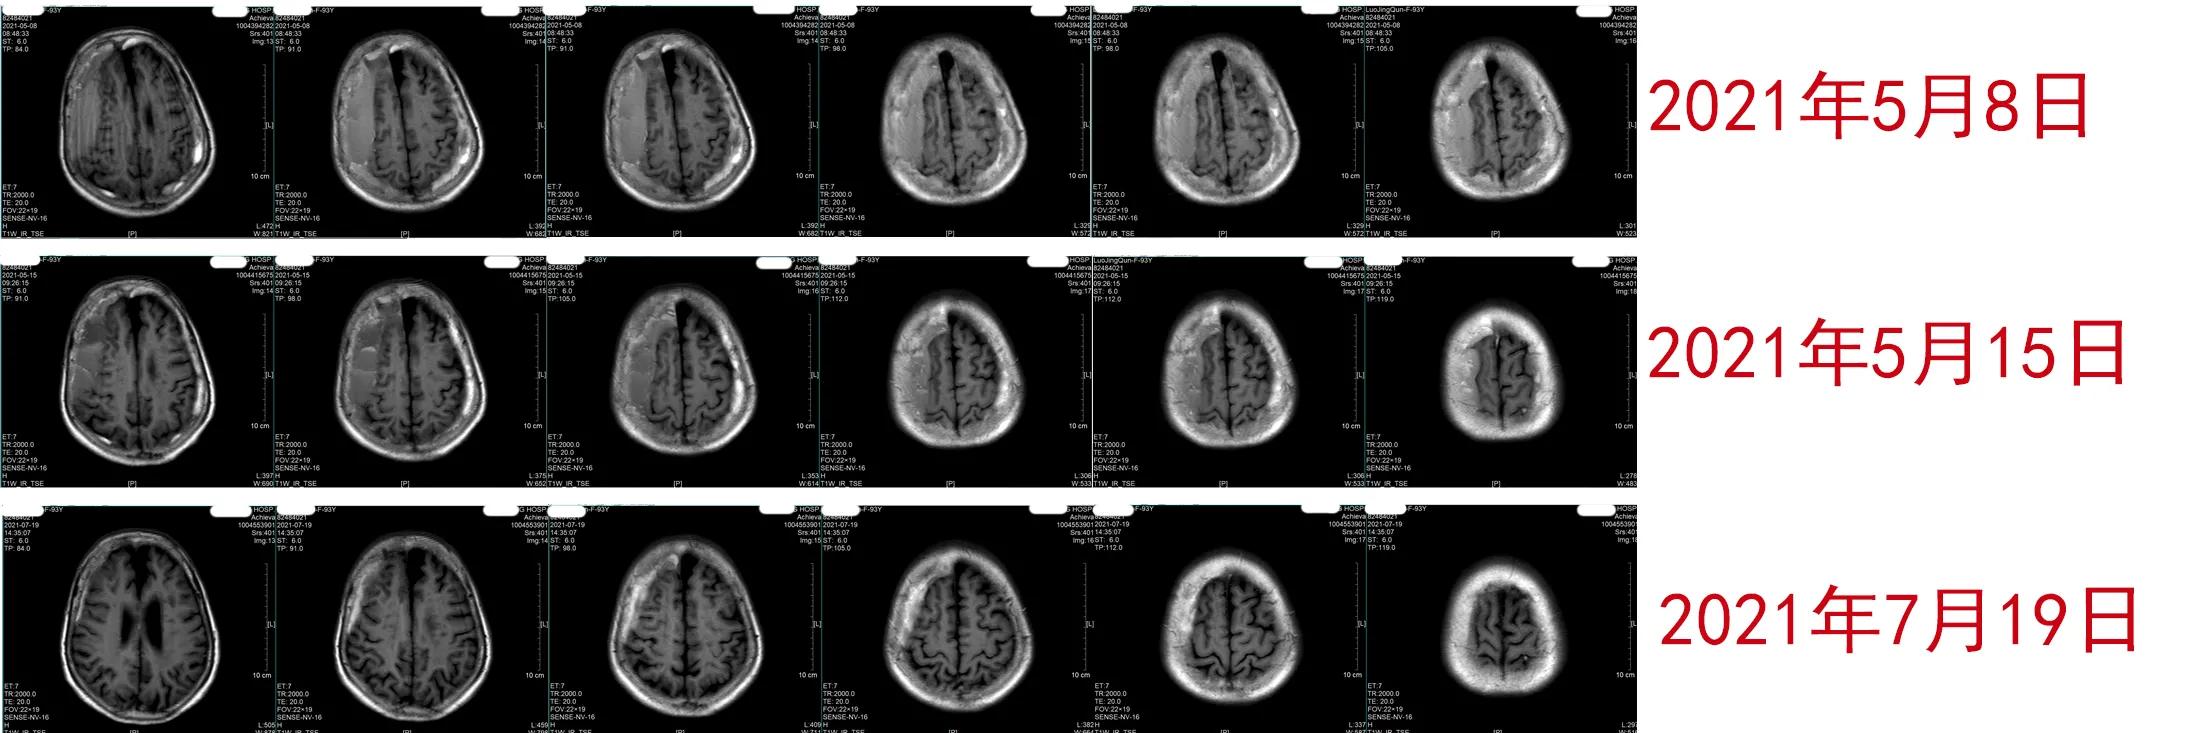

患者LMQ,93岁,是一名安逸的老太太。她平时身体很好,凡事都亲力亲为。今年3月20日,因为自己洗澡,摔了一跤,头破血流的。家人平时非常孝顺,这下都慌了神,在几天内,先后给做了3次头CT,以确定是否有颅内出血,结果都没有明显的异常发现,不禁松了一口气。但约半个月后,老人家开始头晕,复查CT,仍然没有明确颅内有异常,但仔细看,好像左侧形成了硬膜下血肿。套用江湖老话 “没有无缘无故的爱”,实际上也 “没有无缘无故的硬膜下血肿”。显然外伤是导致这个血肿的原因。再过20多天,老人出现左侧肢体无力,终于确诊为硬膜下血肿,多数医生都建议手术。她的家人担心高龄老人禁不起手术折腾,一片慌乱。但是,他们看老人除了走路不能像以前那样走远之外,精神意识完全正常,起居也未受到明显的影响,转诊到某著名神经外科。该医院的神经外科医生听过我的课,向家属介绍了我,邀请我过去面诊。说实在的,自从我从事神经重症专业以来,我经常出去会诊,但都是为重型脑损伤患者诊疗,还真没有专门为慢性硬膜下血肿患者会过诊。我跟这位神经外科朋友说,我可以在电话里会诊,不必远行。但我的朋友却说,家属很相信我,一定要面诊。我连夜赶到这家医院时,老人家因为白天在保姆扶助下走了一小段路,有点疲劳,已经入睡。我不得不将她唤醒。看她精神状况尚好,饮食无碍,就详细问病史,仔细查神经体征,查看影像学和治疗记录,作出短时间内应该不会出现脑疝判断后,决定应用立普妥加地塞米松治疗方案。由于是面诊,我可以详尽地向家属及同行朋友介绍我的治疗理念以及治疗中需要注意却极其容易为患者和家属忽略的细节,并交待了可能发生的副作用和应对方法。我鼓励他们,我用药物治疗过16位90岁以上的硬膜下血肿超级老人(≥90岁),战绩是100%治愈。LMQ老人被我治愈的概率也非常大,这极大鼓舞了家属和患者。我的方案很简单:每天1粒20mg立普妥,一直服用到血肿吸收为止;同时加服4周地塞米松,从3片/次,1天1次,持续1周开始,用4周时间逐步减量到停药即可。出于信赖,老人的家人并不因为我给出这么简单的方案而觉得我在慢待他们,反而极其感谢我为他们提供了非手术方案。我们相约1周后复查影像学,并请医生将患者治疗中的不适反应及时告知我,我来帮助处理。结果,治疗第三天,患者即出现睡眠困难,我判断跟激素有关,给予对症治疗后缓解;治疗1周,不仅患者的左侧肢体力量得到改善,头晕减轻;而且头磁共振检查验证了她的血肿开始减少,虽然减少得还很少,但已经有了希望,再次激励了患者和家属。2周后,医生朋友发来老人家在花园里独自行走的视频并解释因为疫情缘故,老人家没能及时复查头MRI,但承诺尽快去复查。今天,我才见到老人家治疗约2个多月后的磁共振复查影像:我欣喜地发现患者的血肿已近乎完全吸收,神经症状和体征也完全消失……

在这平凡的夜晚,我在北方这座中国神经外科发源之城中独自欣赏着着老人历次治疗的影像变化(图),不禁给自己倒了杯酒,自斟自饮地为这位我并不熟悉的老人家的康复庆贺,为慢治疗再次被成功验证而庆贺。这就是医生的快乐。这种快乐也许永远都不被人理解,也无需被理解……